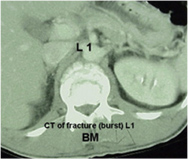

TC (tomografía [axial] computarizada): la TC presenta imágenes de los huesos mejor que de los nervios y se suele usar para mostrar la forma y el tamaño del canal vertebral.